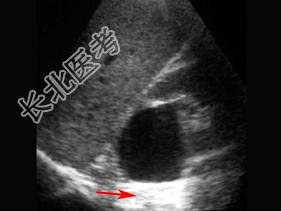

- 单项选择题红色箭头所指部位是 ( )

A、后部回声增强

B、声影

C、无回声

D、强回声

E、等回声